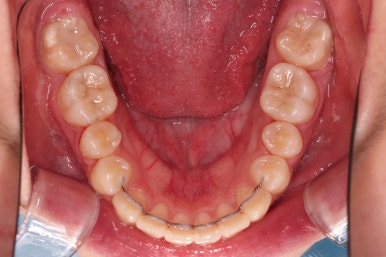

연산동치과 초진 시, 입안의 모습입니다.

보시다시피 앞니쪽이 많이 삐뚤고요. 어금니쪽이 긴밀하지 못한 부정교합이 있네요.

치료 마무리 사진입니다.

연산동치과 전후사진을 비교해 볼게요.

치열이 가지런해지고 교합도 좋아지고 웃는 모습도 매우 좋아졌네요.